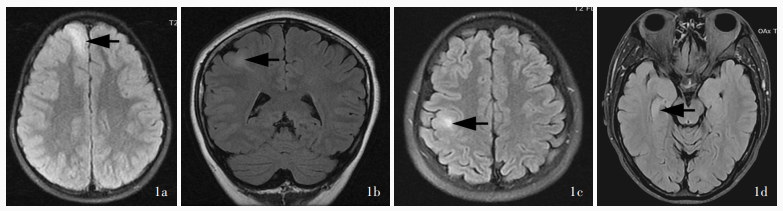

Sun K , Ren Z , Yang D , Wang X , Yu T , Ni D , Qiao L , Xu C , Gao R , Lin Y , Zhang X , Shang K , Chen X , Wang Y , Zhang G . Voxel-based morphometric MRI post-processing and PET/MRI co-registration reveal subtle abnormalities in cingulate epilepsy. Epilepsy Res, 2021, 171: 106568.

doi: 10.1016/j.eplepsyres.2021.106568